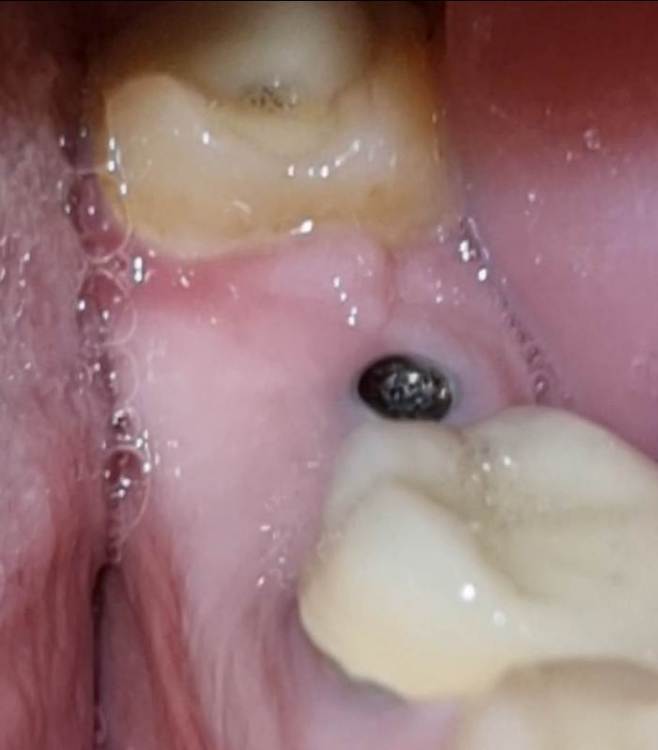

Chelovek2012 Опубликовано 6 декабря, 2023 Автор Поделиться Опубликовано 6 декабря, 2023 (изменено) Скажите, это ОК, или нужно идты к стоматологу снова и подшивать десной? Не болит, температуры нету. Изменено 6 декабря, 2023 пользователем Chelovek2012 Ссылка на комментарий

Irouil Опубликовано 7 декабря, 2023 Поделиться Опубликовано 7 декабря, 2023 Судя по рентген снимку у Вас установлен формирователь десны, если это действительно так - все ок 1 Ссылка на комментарий

Chelovek2012 Опубликовано 7 декабря, 2023 Автор Поделиться Опубликовано 7 декабря, 2023 Если чесно, я не знаю, что это. Я приходил на установку ипланта. 2,5 недели назад мне вставили это вместе с имплантом и сказали придти через 3 месяца. Ссылка на комментарий

АнтонТЛТ Опубликовано 7 декабря, 2023 Поделиться Опубликовано 7 декабря, 2023 Формирователь десны вкручен, перед протезированием его поменяют на широкий 1 1 Ссылка на комментарий

Chelovek2012 Опубликовано 10 декабря, 2023 Автор Поделиться Опубликовано 10 декабря, 2023 07.12.2023 в 14:26, АнтонТЛТ сказал: Формирователь десны вкручен, перед протезированием его поменяют на широкий То есть, нормально, что его видно? Я думал, что вся конструкция будет покрыта десной Ссылка на комментарий

АнтонТЛТ Опубликовано 10 декабря, 2023 Поделиться Опубликовано 10 декабря, 2023 Он должен быть виден, но иногда десну натягивают на него преследуя определенные цели. 1 Ссылка на комментарий

red_butler Опубликовано 11 декабря, 2023 Поделиться Опубликовано 11 декабря, 2023 18 часов назад, Chelovek2012 сказал: То есть, нормально, что его видно? Я думал, что вся конструкция будет покрыта десной это один из вариантов установки формирователя десны Ссылка на комментарий